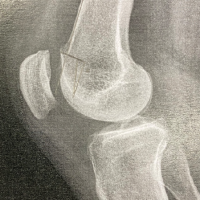

A 16-year-old boy presented to our outpatient department with a history of recurrent patellar dislocation in his right knee for the past 3 years. He also complained of a deformity of his right knee. On examination, his patella was grossly unstable, dislocating at about 30° of knee flexion (Fig. 1). Whole limb X-ray revealed a lateral mechanical axis deviation of 30 mm from the neutral (normal range – <10 mm) (Fig. 2). The opposite limb was normal. The Q angle of the right lower limb was measured to be 22°, which was abnormal (normal range 13–18°). The right knee was in valgus with a tibio-femoral angle of 15° (Fig. 3). The mechanical medial proximal tibial angle was 87.8° which was normal (normal range 85–90). However, the mechanical lateral distal femoral angle was 81°, which was abnormal (normal range 85–90) (Fig. 4 and 5). Hence, it was the distal femur that contributed to the genu valgum. The tibial tubercle–trochlear groove distance was 17 mm, which was normal (normal – under 20 mm), signifying that there was no rotational deformity. The Insall-Salvati ratio was 1.2, which was also normal (range – 0.8–1.2). Magnetic resonance imaging (MRI) revealed a Dejour Type D trochlea dysplasia (Fig. 6) with a trochlear depth of 1.2 mm (normal >3 mm) and a sulcus angle of 172 (normal <140). MRI also revealed an MPFL tear. The factors contributing to the patellar instability were recognized as the unacceptable genu valgum, trochlear dysplasia, and the MPFL tear. Considering that the patient had attained skeletal maturity and to avoid multiple procedures, a decision was made to correct all the anatomical abnormalities as a single procedure.